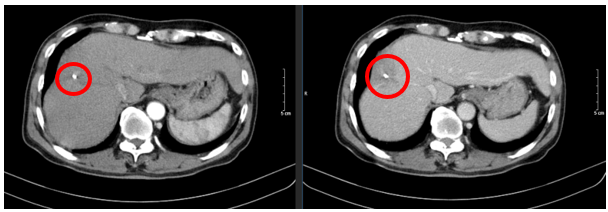

– Chụp cắt lớp vi tính ổ bụng:

Hình 1: Hình ảnh chụp cắt lớp vi tính ổ bụng: Nhu mô hạ phân thùy S7-8 có khối (vòng tròn đỏ) tỷ trọng hỗn hợp kích thước 81x51mm gồm phần tăng tỷ trọng của vật liệu can thiệp và nhiều bóng khí tạo thành ổ tụ khí trong nhu mô kèm phần hoại tử dạng dịch, không có huyết khồi.